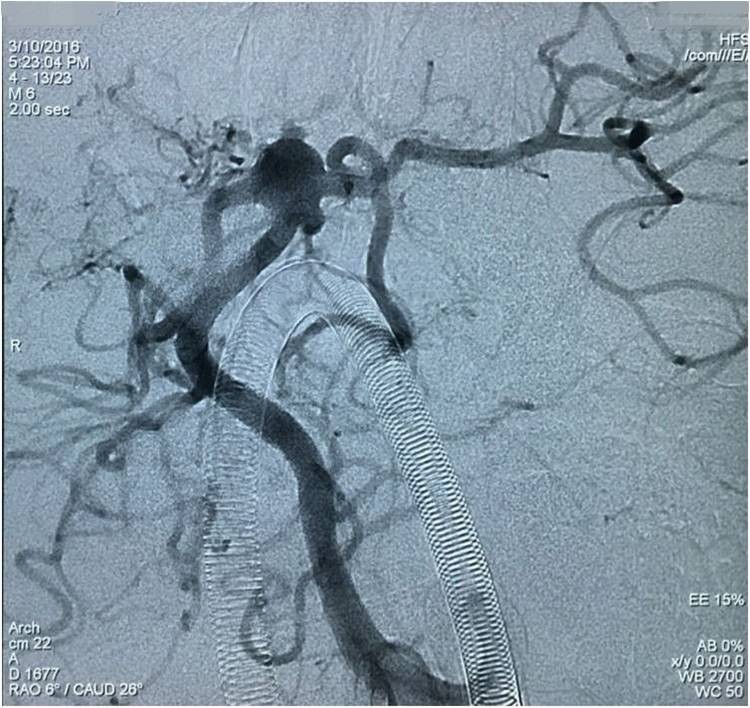

▼左椎动脉工作位造影,可以清晰暴露基底动脉顶端动脉瘤及其子瘤、左小脑上动脉瘤。

▼Headway17导入左PCA P2段,用于备放LVIS JR支架;Echelon10微导管送入基底动脉顶端动脉瘤瘤腔内,送入第一枚弹簧圈QC-4-12-3D,弹簧圈送出约一半长度,在瘤腔内盘旋,一定程度上能有助于防止后续释放的支架陷入瘤腔。

▼经预置的Headway17送入LVIS JR 3.5*23支架,跨瘤颈释放入左PCA-基底动脉内,蒙片显示支架张开良好。